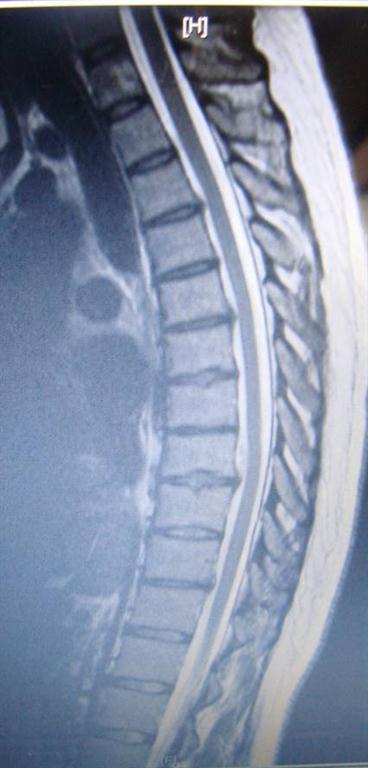

Although uncommon, a small percent of thoracic discs may herniate and cause pain.

Since the anulus fibrosus is very pain sensitive, a contained disc causes back pain and, if the contained disc presses on a spinal nerve, may cause radiating pain into the ribs and side in front of the chest.